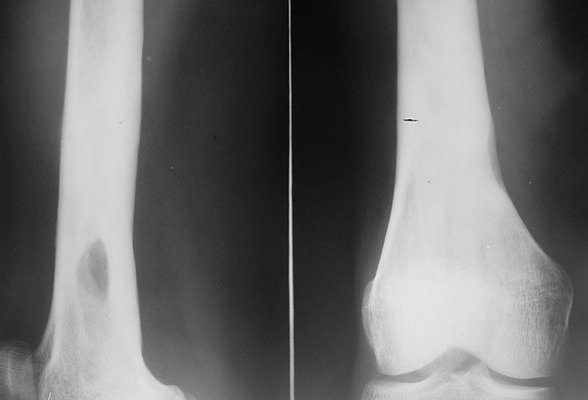

Sechestru osos la nivelul tibiei

Proces de osteomielită la nivelul gambei

Abcesul Brodie